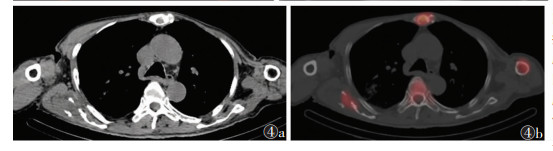

2 结果49例共91处疼痛部位,发生于颅骨颈椎(图 1)、肋骨、髋关节(图 2)、骶髂关节(图 3)、胸椎(图 4)等处的疼痛较剧烈且为持续性疼痛,夜间更明显,并随时间推移逐渐加重,常规非甾体药物缓解不明显。SPECT/CT融合断层显像示阳性40处,其中真阳性35处,假阳性5处;阴性51处,其中真阴性49处,假阴性2处。SPECT/CT融合断层显像对肿瘤疼痛骨转移瘤诊断的敏感度为94.6%(35/37)、特异度为90.7%(49/54)、准确率为92.3%(84/91)。后经病理及临床随访证实5处假阳性病灶中3处为退行性病变,由于存在隐匿性骨质破坏导致骨代谢增高,核素浓聚;余2处,1处为髓腔炎症所致,1处为原发骨肿瘤。2处假阴性病灶由于病灶体积较小,1处位于胸椎重叠部位,1处示溶骨性改变,最后融合显像显示放射性浓聚不明显而导致漏诊。

| 图 4 男,75岁,前列腺癌骨转移,肩胛骨及胸骨2处疼痛 图 4a 胸廓及肱骨CT平扫示:左肱骨近端及中下段可见膨胀性骨质破坏,骨质密度增高,胸骨及右肩胛骨、左侧第9后肋可见类似改变;T10椎体可见片状骨质密度增高影 图 4b SPECT/CT融合平扫显示:左肱骨、胸骨及右肩胛骨、左侧第9后肋溶骨破坏区未见明显放射性浓聚,边缘骨质密度增高区可见不同程度放射性改变 |